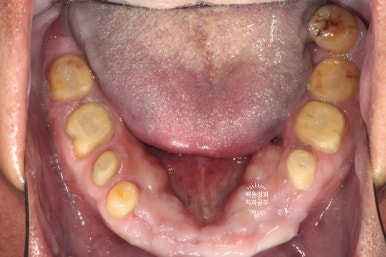

처음 오셨을 때의 상태입니다.

엑스레이를 같이 참고해 보셔야 하는데요,

양쪽 위 큰 어금니가 모두 발치된 상태로 오래 지내신 분이었어요.

보시면 상대적으로 아래 앞니가 머리가 매우 조금만 남아있는 것을 보실 수 있으실텐데요,

아래 앞니가 저렇게까지 극적으로 사라지게 된 경위를 살펴보자니

위 어금니가 없는채로 오래 지내시다보니

주로 앞니로 식사를 하게 됩니다.

위 앞니는 금속-도재 고정성보철물(PFM bridge)로 제작이 되어있는데요, 도재가 씌워진 보철물에 의해 아래 앞니의 마모가 가속화되고

결국 아래 앞니의 머리가 없어질때까지 깨지고 닳고.. 그런 과정을 거치게 된 것이죠.

대구치의 상실은 교합의 붕괴에 가장 큰 영향을 주는 것 같습니다.

아래 앞니의 마모도가 상당히 심합니다.

치과에서 교모(attrition)라고도 하는데요, 머리가 닳아 없어지다보니 치아 내부의 신경관이 드러나게 되고

그렇게 발생한 치통을 해결하기 위해 신경치료를 모두 받으셨던 흔적도 보여요.

여튼.. 심각합니다. 치료가 시급한 상태셨어요.